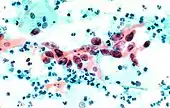

The stain should result in cells that are fairly transparent so even thicker specimens with overlapping cells can be interpreted.[2] Cell nuclei should be crisp, blue to black on color[12][13] and the chromatin patterns of the nucleus should be well defined. Cell cytoplasm stains blue-green and keratin stains orange in color.[13][5]

Eosin Y stains the superficial epithelial squamous cells, nucleoli, cilia, and red blood cells.[2] Light Green SF yellowish confers a blue staining for the cytoplasm of active cells such as columnar cells, parabasal squamous cells, and intermediate squamous cells.[14] Superficial cells are orange to pink, and intermediate and parabasal cells are turquoise green to blue.[12]

.jpg.webp) Squamous Cell Carcinoma, bronchial washing.

Benign urine cytology sample. Squamous cell carcinoma in the cervix.

Squamous cell carcinoma in the cervix.